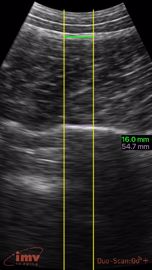

crédit : Laurent Boscher

Le doute, en effet, n'a pas sa place en matière de gestation porcine. Les deux éleveurs ont choisi un matériel dont ils vantent la fiabilité : un Duo-scan Go d'IMV imaging. Même si son coût est un peu supérieur à celui d'autres appareils (importés), « rapporté à l'animal, c'est minime ! Nous avons 3 500 portées par an ! », précise François Pinsault. Cette rentabilité peut même être encore augmentée, puisque le même appareil peut servir aux mesures d'état corporel (ELD) des animaux, par exemple lors de la 2e échographie de gestation.